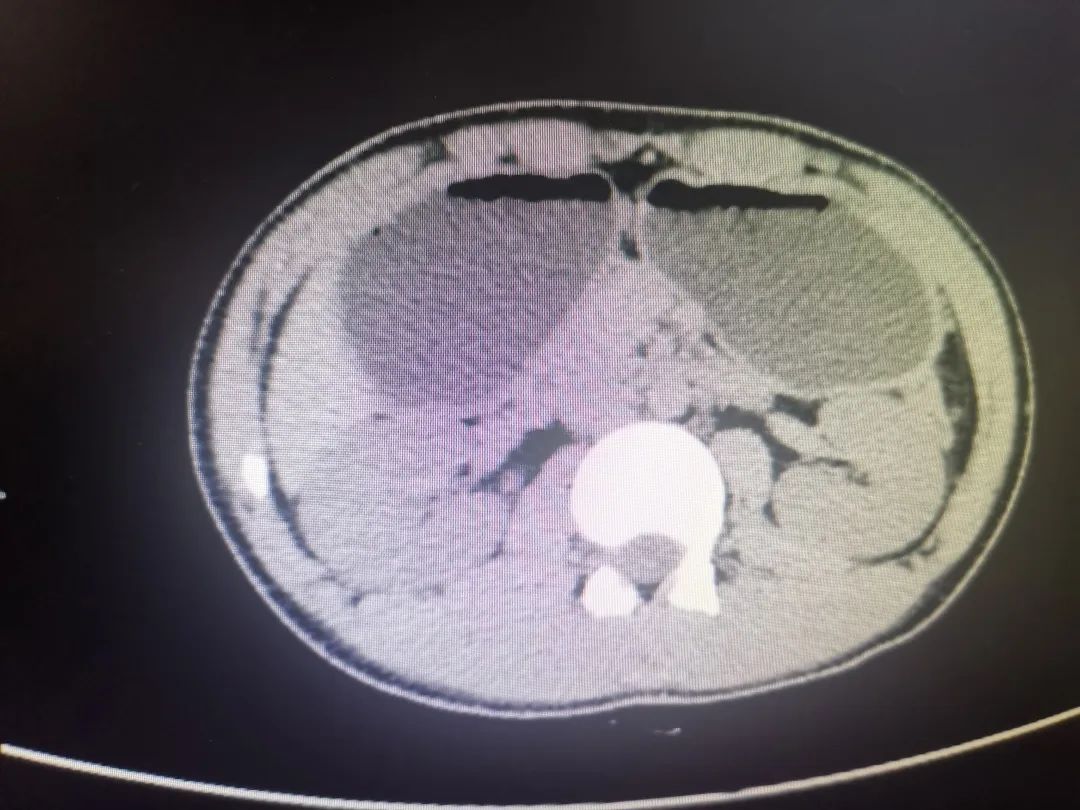

不吃早飯、暴飲暴食、 吃飯不準(zhǔn)時(shí)、愛(ài)點(diǎn)快餐外賣 ······ 這是當(dāng)代不少年輕人的飲食習(xí)慣 最近 江蘇省中醫(yī)院普內(nèi)科 就收治了一名年輕的患者 雖然只有15歲 卻因長(zhǎng)期不規(guī)律的飲食習(xí)慣 引起十二指腸降部潰瘍 導(dǎo)致針孔樣狹窄 出現(xiàn)嘔吐等嚴(yán)重癥狀 高中少年嘔吐不止 最多時(shí)吐了2000多毫升胃液 15歲的振宇(化名)來(lái)自泰州,二周前因咽痛、鼻塞流涕等,服用感冒藥次日出現(xiàn)惡心嘔吐,吃什么吐什么,而且上腹部陣陣疼痛。起初家人未特別重視,以為是得了急性胃腸炎,在當(dāng)?shù)蒯t(yī)院輸液治療1周,但癥狀未見(jiàn)好轉(zhuǎn),嘔吐越來(lái)越嚴(yán)重。家長(zhǎng)開始緊張擔(dān)心,經(jīng)人推薦送到了江蘇省中醫(yī)院,住進(jìn)了普內(nèi)科病房。 “入院時(shí),該患者神情疲乏,惡心嘔吐不止,吃不好睡不好,形體消瘦,1米67左右的個(gè)子,體重只有50kg左右!逼諆(nèi)科主任陸為民介紹,全腹部CT顯示,患者胃內(nèi)有很多潴留液,一吃東西就吐,血液生化、動(dòng)脈血?dú)夥治龅葯z查結(jié)果顯示,患者已經(jīng)出現(xiàn)了急性腎功能損傷、代謝性堿中毒、低鉀、低鈉、高尿酸血癥等癥狀。 但入院第二天,振宇又開始覺(jué)得上腹部脹滿,隨之嘔吐了約2000多毫升的墨綠色胃內(nèi)容物。經(jīng)胃鏡檢查,發(fā)現(xiàn)胃內(nèi)有大量黃綠色液體潴留,局部見(jiàn)0.5cm潰瘍。 ▲胃鏡檢查顯示,患者十二指腸降部潰瘍引起針孔樣狹窄 “該患者由于十二指腸降部潰瘍引起針孔樣狹窄,吃的東西根本下不去,所以導(dǎo)致惡心嘔吐,并出現(xiàn)急性腎功能損傷、水電解質(zhì)及酸堿平衡紊亂!标憺槊裰魅握J(rèn)為,患者因?yàn)槭改c降部狹窄梗阻,反復(fù)嘔吐時(shí)間較長(zhǎng),出現(xiàn)了嚴(yán)重的并發(fā)癥,容易并發(fā)胃腸功能的衰竭。 ▲陸為民主任正在為患者查房 經(jīng)過(guò)積極治療,目前振宇的癥狀已基本緩解,精神面貌改善,整體恢復(fù)良好。醫(yī)生建議1個(gè)月左右復(fù)查胃鏡觀察他的潰瘍愈合情況。 潰瘍病容易導(dǎo)致并發(fā)癥 不規(guī)律飲食是“禍根” 潰瘍病一般是指胃潰瘍和十二指腸潰瘍,其發(fā)作呈周期性,發(fā)作期和緩解期交替出現(xiàn),發(fā)作期間常伴有腹痛!盡管潰瘍病是一種常見(jiàn)疾病,但它引起的并發(fā)癥危害極大,如幽門梗阻、十二指腸梗阻、出血、穿孔等并發(fā)癥,嚴(yán)重者可危及生命,少部分胃潰瘍甚至?xí)䦟?dǎo)致癌變。”陸為民主任介紹。 振宇的父親介紹,振宇從小體質(zhì)就比較弱,以前偶爾也有嘔吐的“毛病”,去年夏天游泳回來(lái)后吹了空調(diào),當(dāng)天凌晨便開始嘔吐,送到當(dāng)?shù)蒯t(yī)院輸液后,沒(méi)兩天就好了,以為身體受涼就沒(méi)當(dāng)回事。父親顯得有些愧疚,要是早點(diǎn)重視起來(lái)就好了。據(jù)了解,振宇平時(shí)住校,早晨6點(diǎn)多上課,經(jīng)常起床洗漱完不吃早飯就直接跑去上課,晚上也常吃油炸燒烤等夜宵,到23點(diǎn)多睡覺(jué)更是常事。 如今,年輕人得消化性潰瘍很常見(jiàn),陸為民主任解釋,這和長(zhǎng)期不規(guī)律的飲食習(xí)慣有著密切的關(guān)系。最近,陸為民主任的門診平均每天都有20多個(gè)左右消化道系統(tǒng)疾病的年輕患者前來(lái)就診,“年輕人長(zhǎng)期不規(guī)律的飲食習(xí)慣,再加上運(yùn)動(dòng)少,壓力大,經(jīng)常熬夜,情緒不穩(wěn)定等因素都會(huì)誘發(fā)潰瘍病的發(fā)生。” 年輕人掌握日常四關(guān)鍵 打造健康的胃腸道 陸為民主任告誡年輕人,身體健康是重中之重,要在完成工作或?qū)W業(yè)的同時(shí),保證適當(dāng)?shù)倪\(yùn)動(dòng)、充足的睡眠和良好的飲食習(xí)慣,以防止消化系統(tǒng)疾病,特別是消化性潰瘍及其并發(fā)癥的發(fā)生。 1.適當(dāng)?shù)倪\(yùn)動(dòng)。(1)要注意勞逸結(jié)合,抽出時(shí)間運(yùn)動(dòng),比如慢跑、騎自行車、游泳、中醫(yī)八段錦、太極拳等。(2)保證“曬太陽(yáng)”的時(shí)間。見(jiàn)不到陽(yáng)光容易骨質(zhì)疏松,適當(dāng)?shù)膽敉膺\(yùn)動(dòng),多曬曬太陽(yáng),有利于保持胃腸功能的健康。 2.充足的睡眠。睡眠充足不僅可以增加機(jī)體抵抗力,緩解疲勞,提高記憶力和促進(jìn)新陳代謝,也可以增強(qiáng)消化功能,增加對(duì)營(yíng)養(yǎng)物質(zhì)的吸收及利用。 3.良好的飲食習(xí)慣。(1)要注意“質(zhì)”。保證營(yíng)養(yǎng)均衡,瘦肉、魚、雞蛋、牛奶等蛋白質(zhì)要攝入足夠,多吃新鮮的蔬菜、水果以及清淡易消化食物,少吃快餐外賣等高油高糖高能量食品。(2)要注意“度”。注意食物的溫度,食物不能太涼、太燙,尤其是夏季很多人愛(ài)吃冷飲,以圖一時(shí)之快,時(shí)間一長(zhǎng)容易導(dǎo)致胃粘膜受損,供血減少,影響胃分泌、動(dòng)力等,從而引起炎癥潰瘍。注意吃飯的速度,充分咀嚼,細(xì)嚼慢咽。注意食物的軟硬度,飲食應(yīng)偏軟些,少吃油炸、燒烤等偏硬的食物。此外,有潰瘍病史的患者,竹筍、蘆蒿等粗纖維的要盡量少吃或不吃。(3)要注意“量”。切忌暴飲暴食,食物攝入量突然增加,超過(guò)胃容量的正常水平,輕者會(huì)影響消化系統(tǒng)功能,重者會(huì)導(dǎo)致急性胃擴(kuò)張、胃穿孔,甚至還可能誘發(fā)急性胰腺炎而危及生命。(4)要注意“節(jié)”。人的胃是有節(jié)律性的,尤其不要因?yàn)闆](méi)時(shí)間、不喜歡、不餓或不想吃、節(jié)食減肥等而不吃早餐,如果饑飽不定,很容易打破消化系統(tǒng)的節(jié)律性,所以一日三餐要定時(shí)有規(guī)律。 4.加強(qiáng)心理調(diào)節(jié)。人的消化功能會(huì)隨著情緒波動(dòng)而出現(xiàn)“情緒化”的反應(yīng)。眾多能夠影響自主神經(jīng)功能的異常刺激,如壓力過(guò)大、過(guò)度勞累、情緒緊張、焦慮、抑郁等,都可能導(dǎo)致胃腸蠕動(dòng)減慢,消化液分泌異常,出現(xiàn)各種消化不良癥狀,引發(fā)消化性潰瘍。所以平時(shí)要加強(qiáng)心理調(diào)節(jié),必要時(shí)到心理?七M(jìn)行診斷治療。